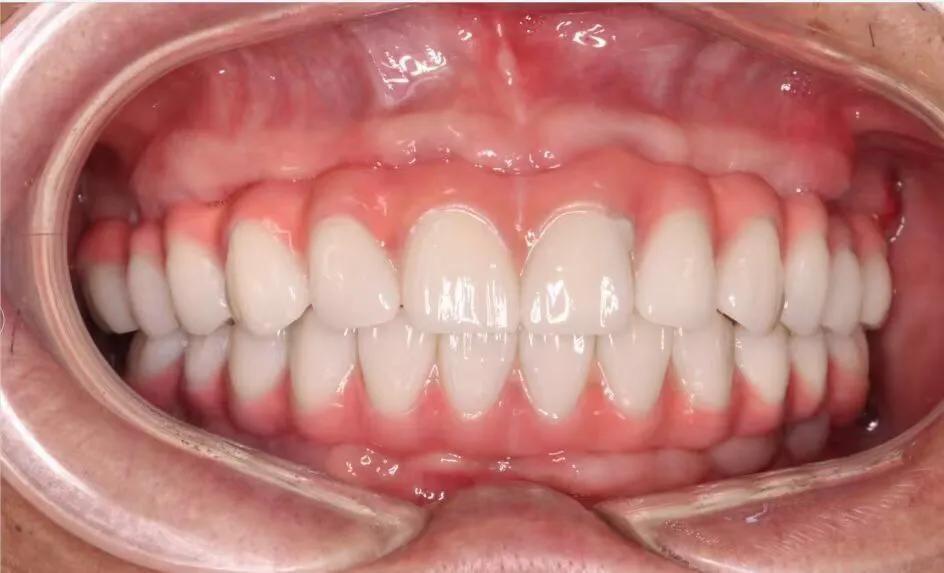

典型的負重,All-On-4。

這就是傳說中的當天戴牙當天吃飯,網(wǎng)上到處宣傳的就是這種種植方法。但是不是每一個人都能做這個,All-on-4一般需要預約,醫(yī)生種植完畢,技師馬上開始取模做牙,大概5小時左右就可以戴上臨時牙回家吃飯了,休息一兩天,正常吃飯是沒問題的。